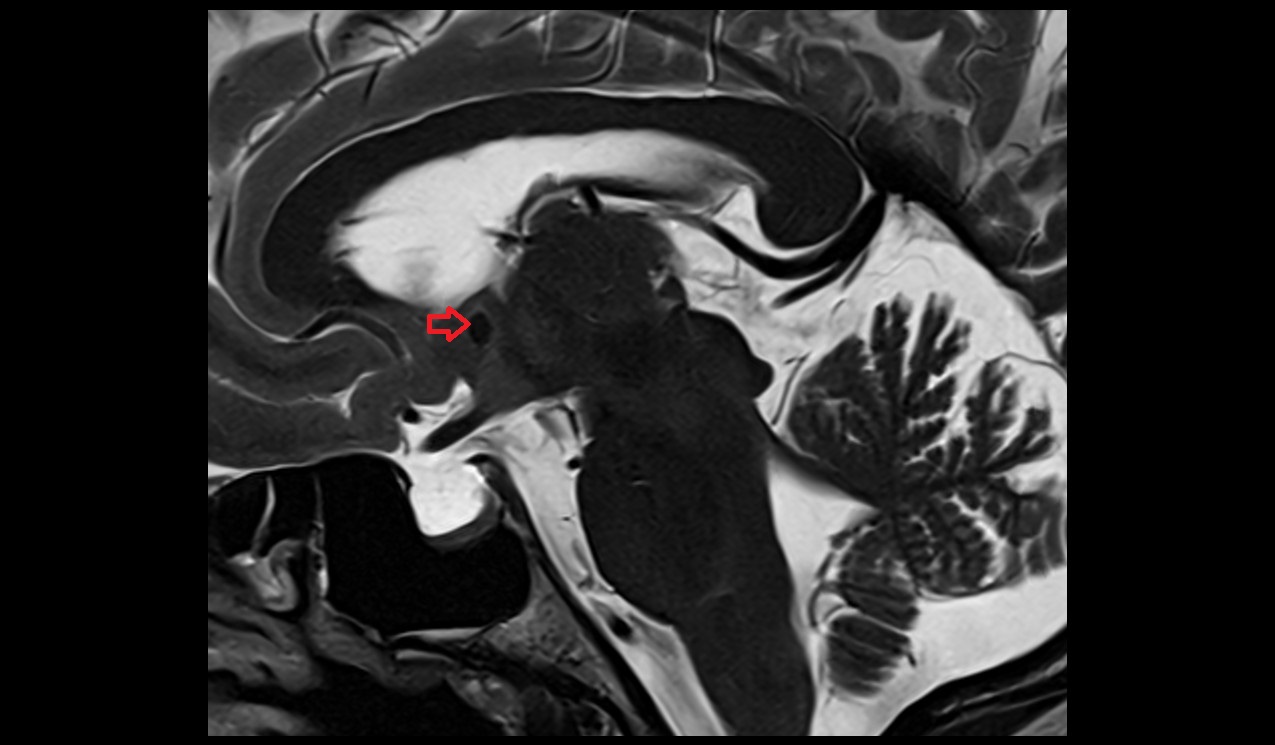

- Pituitary gland

- Pituitary stalk

- Posterior lobe pituitary gland

- Anterior lobe of pituitary gland